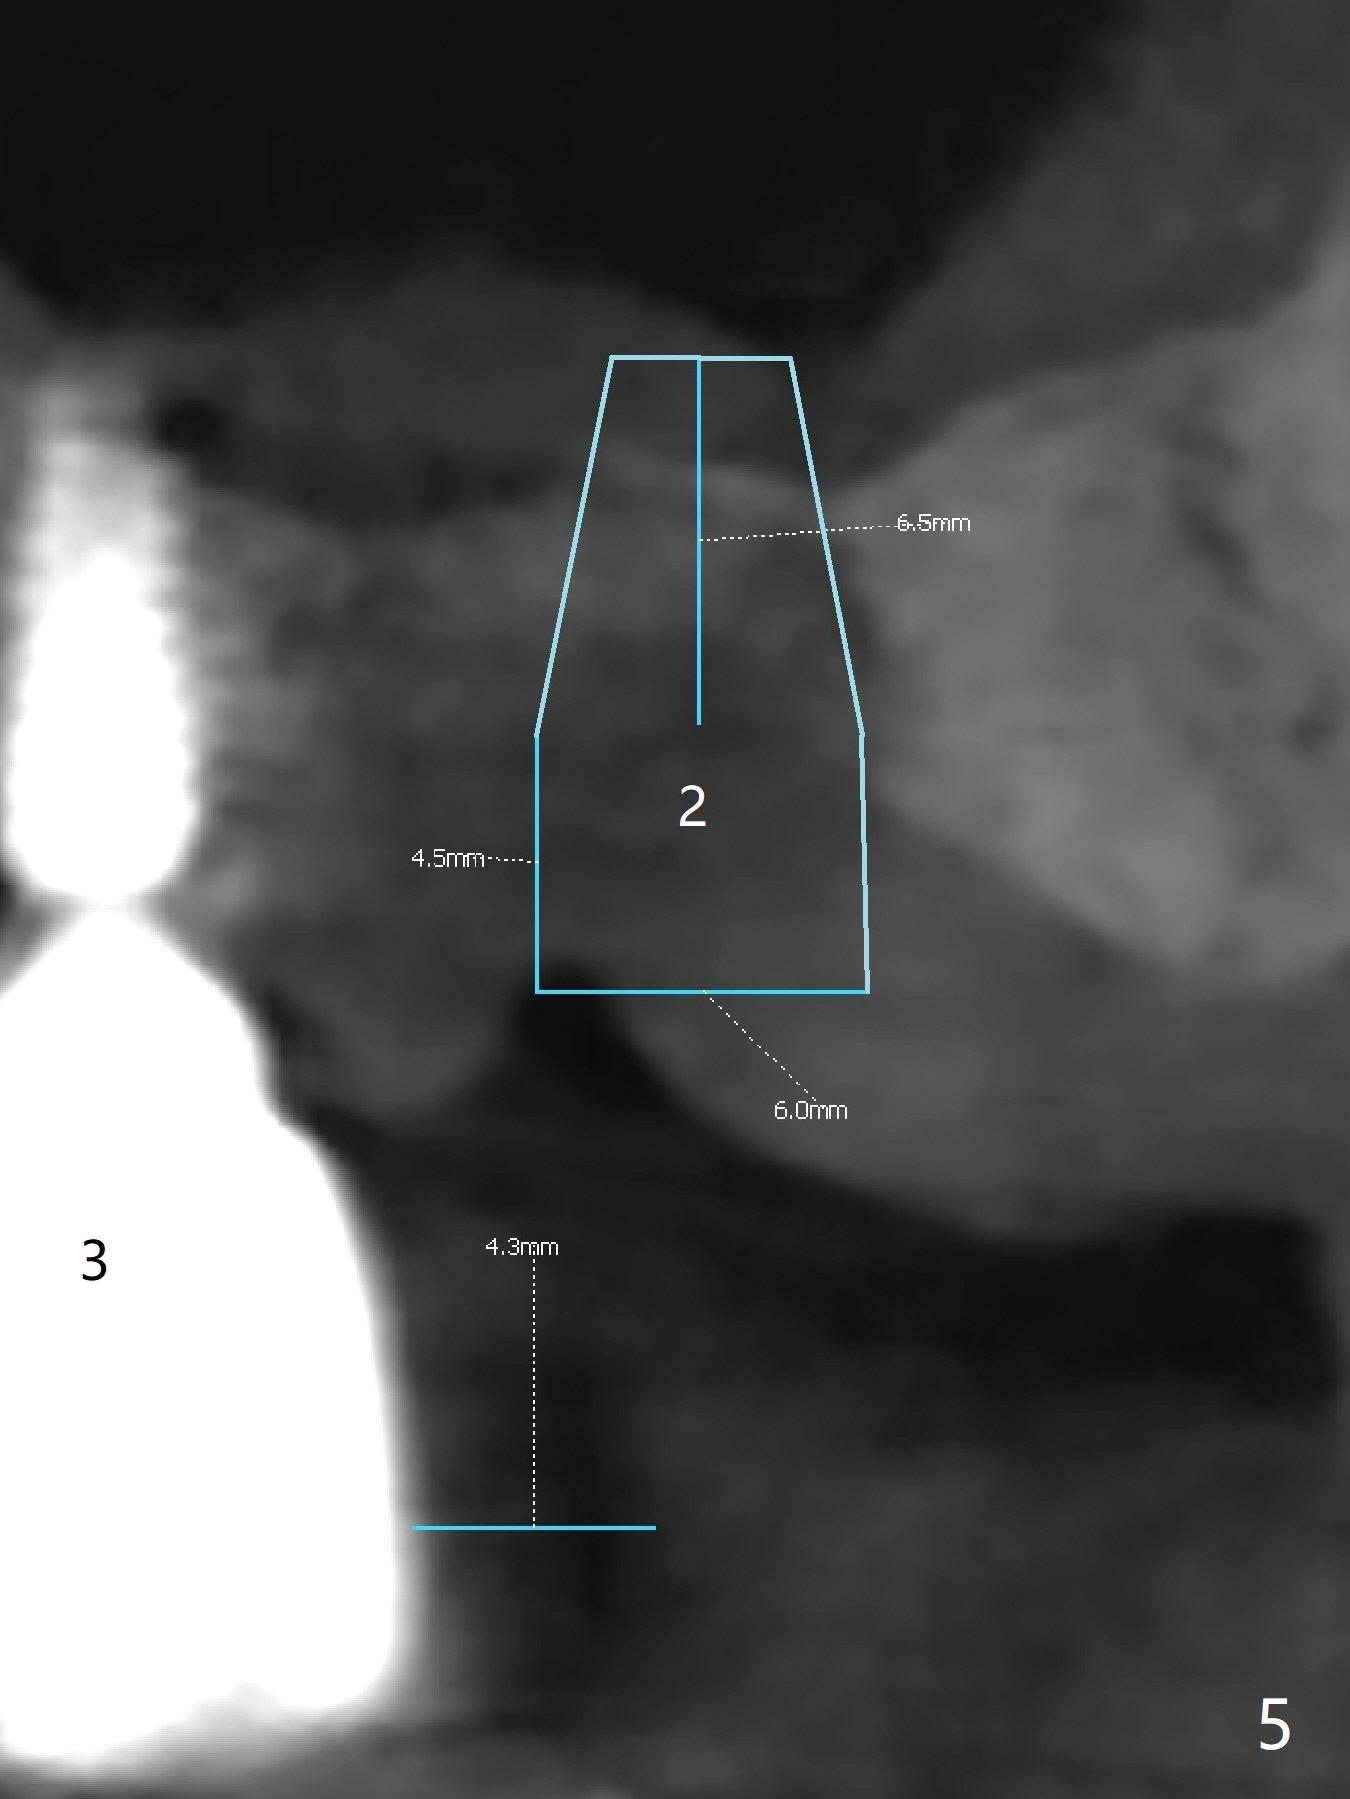

Implant